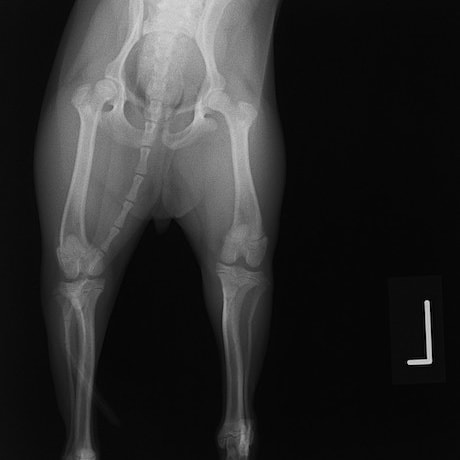

骨盤骨折 : 症例1 | 症例2 | 症例3 | 症例4